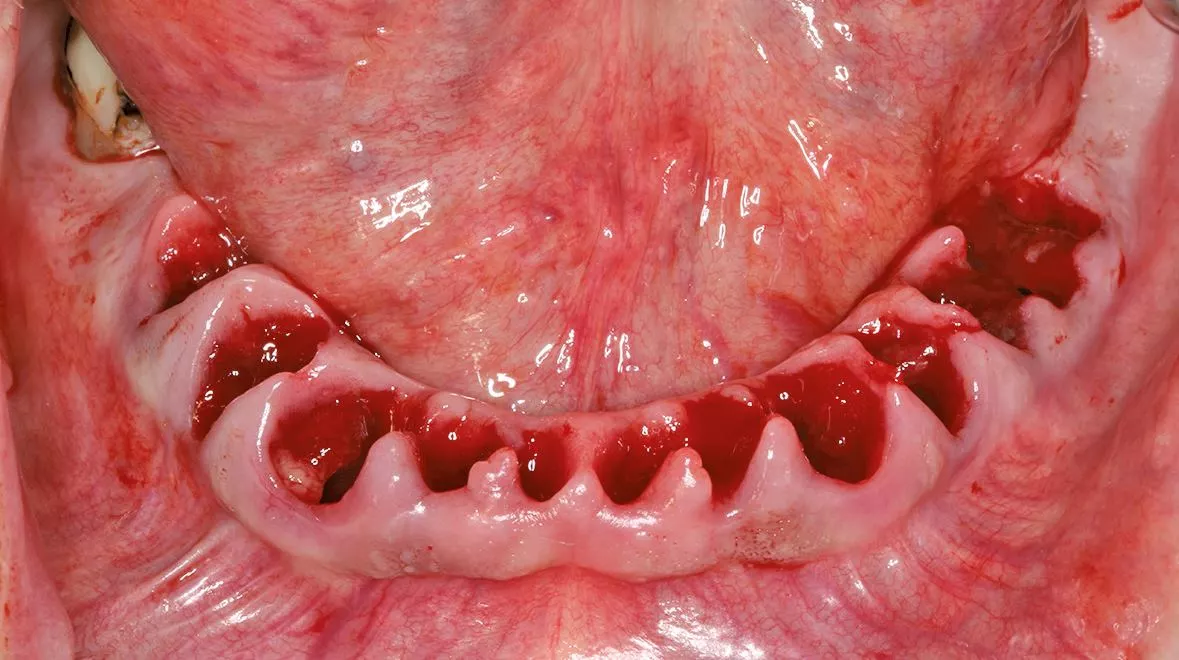

Dies erfordert aber gerade beim digitalen Scan eine vollständige Darstellung des Gaumendachs bis zur A-Linie. Im zahnlosen Unterkiefer ist eine Abstützung über den retromolaren Bereich möglich, dieser lässt sich aber je nach Intraoralscanner oftmals nicht vollständig abbilden. Bei einer Sofortimplantation können die Zähne, die nicht durch ein Implantat ersetzt werden zunächst für die Abstützung der Schablone belassen werden. Alternativ hat sich auch die Verwendung von Fixationspins etabliert, mit denen die Schablone auf der Schleimhaut abgestützt werden kann [13] (Abb. 9-10).

Dieses Vorgehen wird vor allem bei der sogenannten Flapless-Surgery verwendet, wo auf eine Mobilisation des Mukoperiostlappens verzichtet wird [10]. Bei der Auswahl des Aufbereitungsinstrumentariums kann für eine Navigationsschablone lediglich mit einer Pilotbohrung gearbeitet werden und es folgt die weitere Aufbereitung mit dem standardmäßigen Instrumentarium. Alternativ wird ein schaftgeführtes Instrumentarium über eine Masterhülse verwendet [2]. Die Vorteile der voll geführten Aufbereitung zeigen sich in einem geringeren Risiko von Verkippungen oder einer zu tiefen Aufbereitung der Kavitäten. Beim Einsetzen der Bohrschablone mit Fixationspins können diese

im Oberkiefer bei dünner Kortikalis oftmals durch ein festeres Einpressen positioniert werden. Im Unterkiefer wird über die Hülse für den Fixationspin in der Regel eine Vorbohrung notwendig. Nach der genauen Lagesicherung der Navigationsschablone kann dann die komplette Bohrerabfolge geführt bis zur Implantatinsertion angewendet werden. Im Anschluss werden die bei der Planung definierten geraden und angulierten Abutments eingesetzt und die Titanzylinder für das Einkleben des Provisoriums fixiert [1]. Nach dem Einkleben der Zylinder in das Provisorium muss diese nochmals ausgearbeitet werden und die Sofortversorgung ist abgeschlossen (Abb. 11-12).